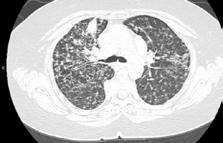

A 58-year-old female with recently diagnosed COVID-19 pneumonia was found to have a dry cough and dyspnoea in the setting of persistent bilateral hilar and mediastinal lymphadenopathy associated with bilateral nodular infiltrates. Of note, she immigrated to the USA from India 10 years prior, with the most recent travel to India 2 years ago. Quantiferon testing upon return to the USA was negative at that time. Workup included bronchoscopy with endobronchial ultrasound revealing non-caseating granulomas with negative stains for acid-fast bacilli (AFB). She was diagnosed with Stage 3 sarcoidosis and initiated on prolonged steroid taper with improvement of symptoms. With taper of steroid dose, however, she developed lymphocyte-predominant exudative effusion with negative cultures, and was reinitiated on a protracted steroid course with rapid symptom resolution. At 4-month follow-up, she had worsening CT findings upon steroid taper, and was started on azathioprine. One month later, she required hospital admission for worsening dyspnoea and fatigue. She was noted to be febrile, tachycardic, and tachypnoeic with worsening

hypoxia. Subsequent CT chest showed progression of bilateral nodular infiltrates with new right upper lobe consolidation and air bronchograms concerning for multifocal pneumonia (Figure 1). Incidentally, she was also noted to have calcified splenic granulomas. She developed rapid clinical deterioration, ultimately requiring mechanical ventilation, pressor support, and continuous renal replacement therapy. Repeat bronchoscopy revealed diffuse alveolar haemorrhage with multiple AFB smears positive for Mycobacterium tuberculosis. She was immediately initiated on quadruple therapy, but unfortunately, despite treatment, developed refractory shock and passed away 2 weeks after initial presentation.

A) Initial adenopathy with peripheral patchy ground glass opacities in the right lung following COVID-19 pneumonia. B) Persistent bulky adenopathy 1 year after initial presentation. C) Extensive nodularity throughout the right lung with increasing confluent opacities in the right upper lobe and stable mediastinal lymphadenopathy 2 years after initial presentation. D) Tuberculosis superimposed on sarcoidosis with progression of nodular infiltrates, worsening right upper lobe consolidation, and air bronchograms with incidental calcified splenic granulomas (not pictured).

Figure 1: CT progression of patient’s sarcoidosis and tuberculosis.